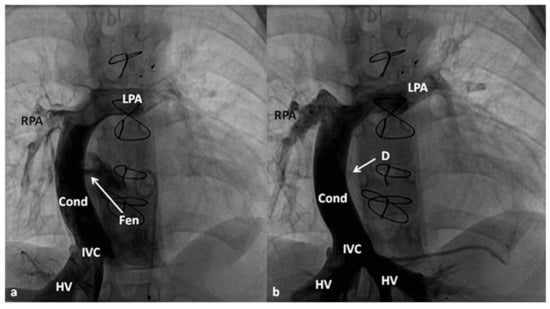

7.2.1. Single-Ventricle Palliation (Fontan)